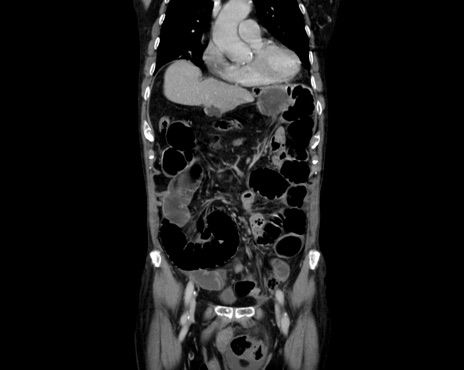

症例26(冠状断像)

【症例】80歳代男性

【主訴】嘔吐

【現病歴】昨晩2回嘔吐あり、今朝になっても嘔吐あり。来院。

【既往歴】胃潰瘍

【身体所見】意識清明、BT 37.6℃、BP 166/95mmHg、HR 100bpm、SpO2 97%、腹部:平坦・軟、腸蠕動音聴取良好、圧痛なし。

【データ】WBC 21900、CRP 1.4

横断像